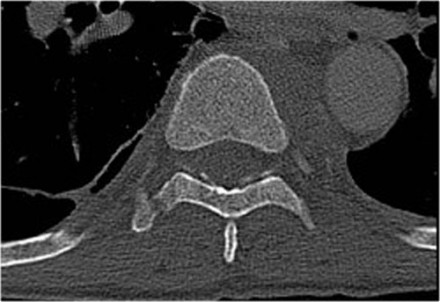

The x-ray of the C-spine in this patient was normal and did not show the fracture.

First look at the first CT-images and decide what is going on.

Then scroll to the next images.

In this case of translation there is bilateral facet dislocation and also a horizontal fracture of the spinous process.

There is severe narrowing of the spinal canal.

Continue with the MRI-images.

Again look at the first MR-images and decide what is going on.

Then scroll to the next images.

The findings are:

- Anterior displacement of C7 to Th1.

- Protrusion of the disc.

- Compression of the spinal cord.

- Bone marrow edema in several vertebral bodies, either due to contusion or fracture.

- Interspinous edema and disruption of the ligamenta flava C7-Th1 and supraspinous ligament Th1-Th2.

In some cases it can be difficult to decide whether there is a translation or distraction injury and we have to assume that the traumtic mechanism is a combination of forces.